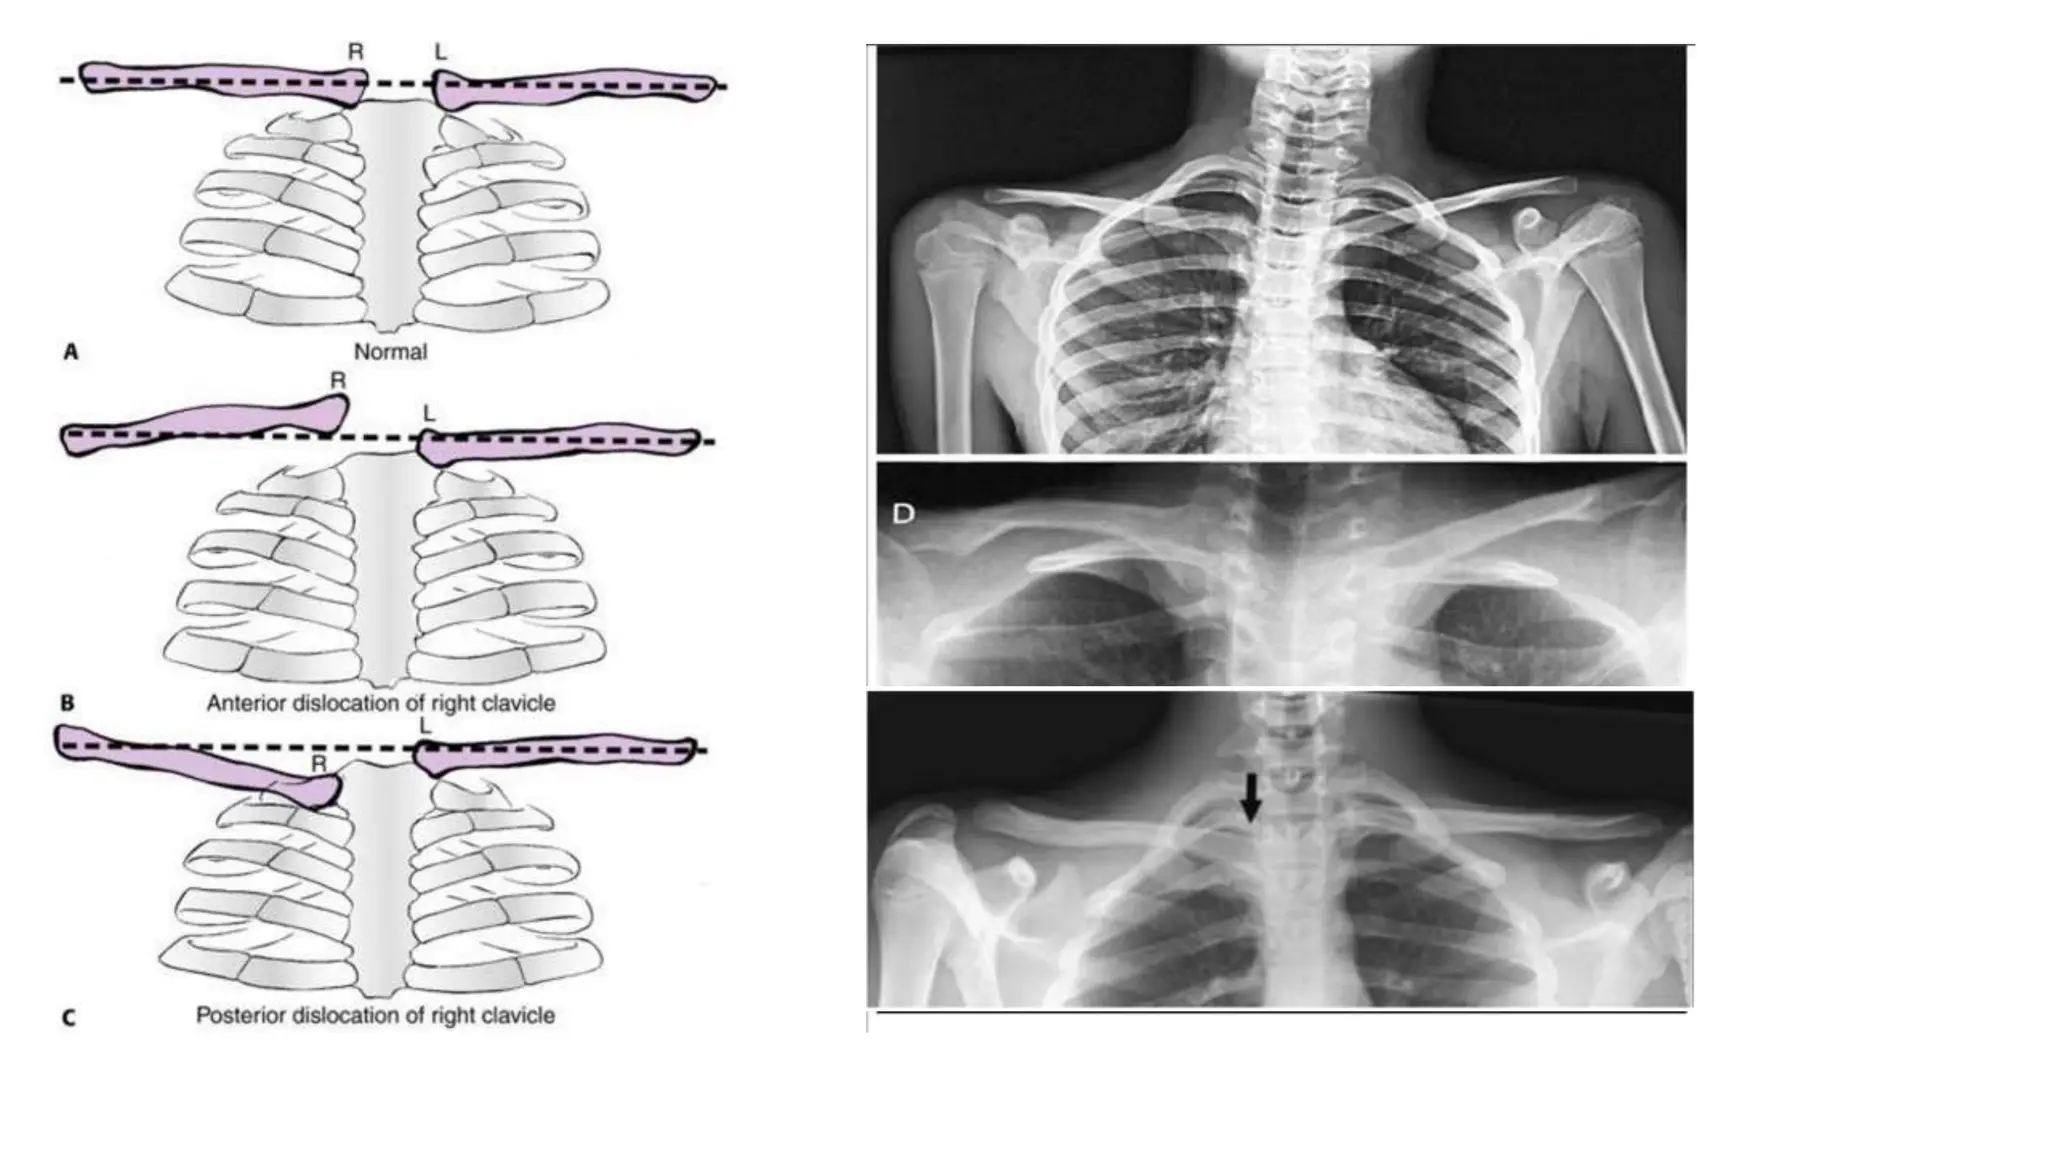

Sternoclavicular injuries

Radiographic evaluation

• Hobbs view

• Serendipity view

• CT:

• Distinguishes injuries of the joint from fractures and minor subluxations

• Substantial asymmetry in joints

Hobbs view Serendipity view